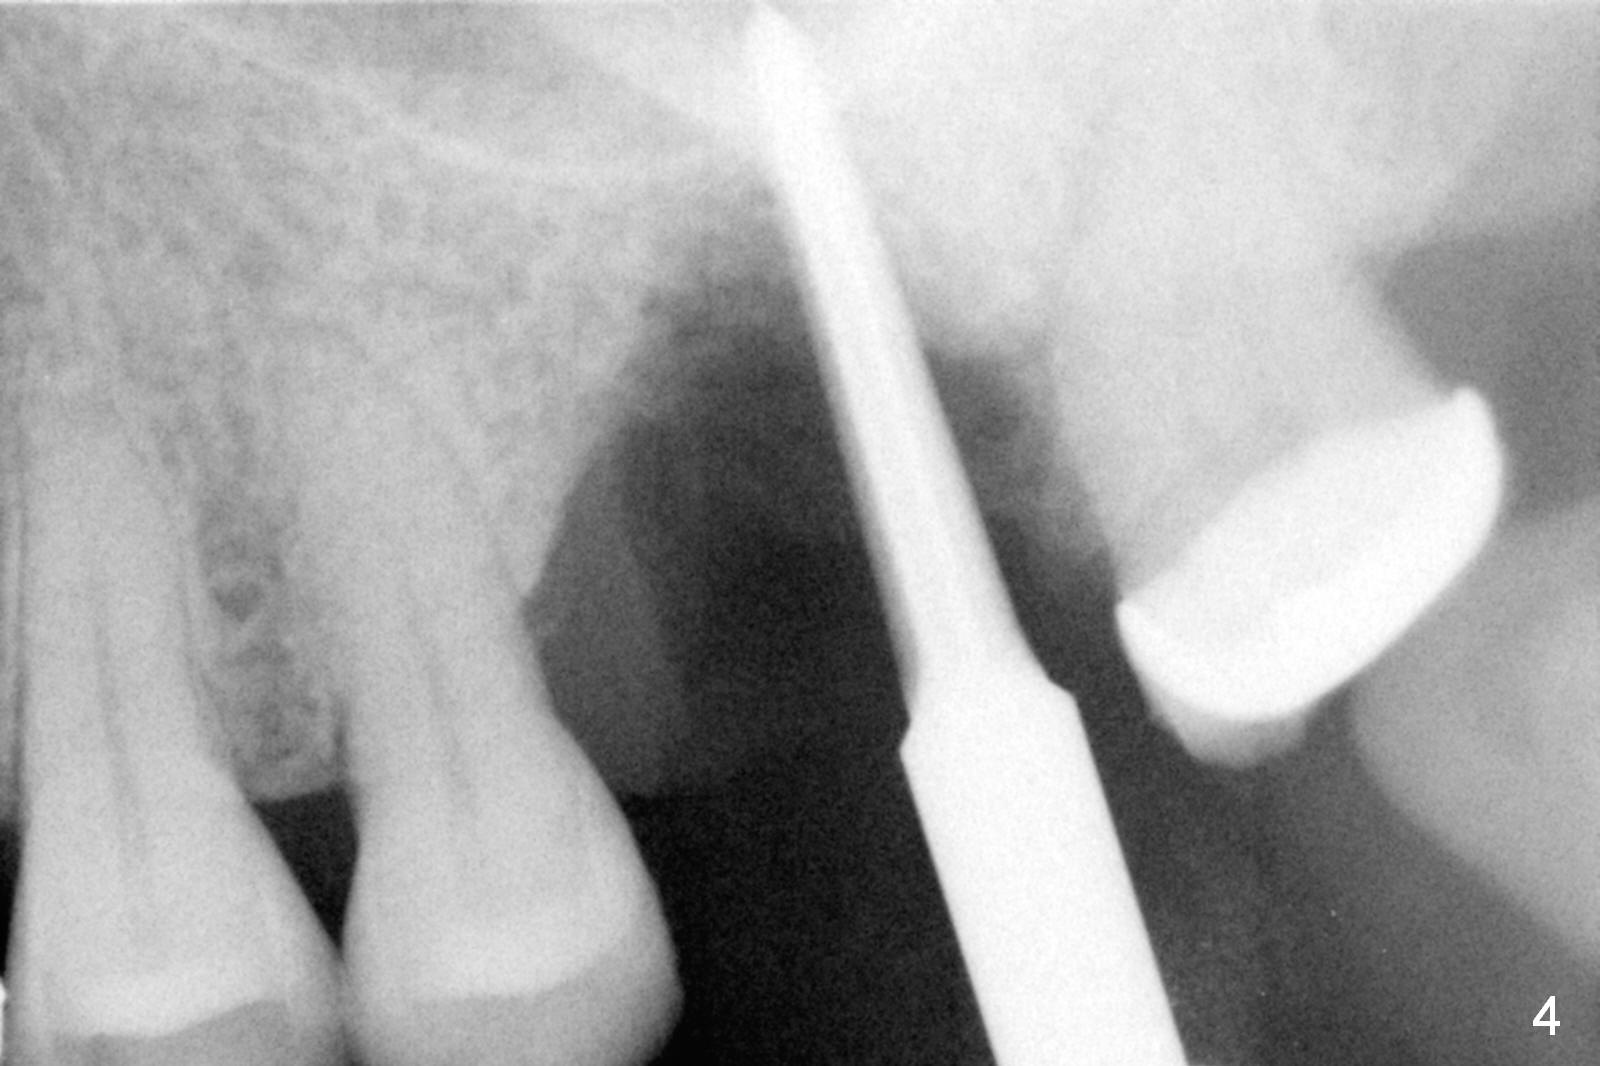

There is abundant subgingival calculus on the surfaces of the extracted tooth at #14 (Fig.1: P: palatal; MB: mesiobuccal), corresponding to the large empty socket (Fig.2 without septal bone, the buccal plate being low). Osteotomy is established palatally with Magic Expander (ME) 3.0 mm for ~ 3 mm deep (Fig.3,4) with minimal stability so that it moves during X-ray taking (Fig.4). Since the bone is dense, Magic drill 4.3 mm is used after application of ME 3.8 and 4.3 mm to complete sinus lift (Fig.5 (panoramic X-ray)). A 5x11 mm implant is placed with ~ 30 Ncm, followed by insertion of 6.5x4(3) mm Hexa abutment, bone graft and collagen membrane (Fig.6). The latter is kept in placed with an immediate provisional with clearance from the opposing dentition (Fig.7 *). Between the 1st and 3rd weeks postop, the buccal gingiva recedes with loss of bone graft (Fig.8 <) and implant thread exposure (Fig.9 * (A: abutment)). After inducing hemorrhage, allograft is placed (Fig.10 >), followed by collagen dressing (Fig.11 >). The wound closes by adding new acrylic (Fig.12 *). Thirteen days later, food is trapped in the buccal gap (Fig.13 ^). It appears that the provisional does not help wound healing. The provisional and abutment are removed; incorporating bone graft (Fig.14 *) and the implant are exposed. After placing collagen plug against the bone graft and implant, the wound is closed by periodontal dressing.